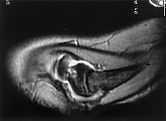

Dado este hallazgo se deciderealizar resonancia magnética (RM) (fig. 2), en la que seobservan imágenes de erosiones subcondrales en la cabezahumeral con señal hipointensa en T1 e hiperintensa en T2,junto con signos de escaso derrame articular, imágenescompatibles con enfermedad de Panner, también denominadaosteocondritis de la cabeza humeral.

Figura 2.Resonanciamagnética de codo derecho. A. Proyección sagitalpotenciada en T2: erosiones subcondrales con señalhiperintensa en epicóndilo lateral. Derramearticular.

Figura 2. B.Proyección axial en secuencia STIR; se confirman lasimágenes hiperintensas y el derrame articular mencionadasanteriormente.